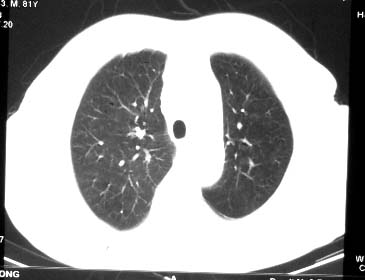

两肺多发异常密度,其中双上肺病变主要为纤维增殖性改变;右中肺内侧段病变密度相对均匀,无恶性特征,周围可见卫星灶和浸润表现,邻近胸膜稍增厚,所见纵隔层面无肿大淋巴结和胸腔积液。提示结核性改变。如果可能建议强化。

右肺中叶团片影,似多病灶融合而成,密度不均匀,边界清楚,周围见明显的索条及小结节,左肺亦见斑片影,纵隔窗未见肿大淋巴结.多考虑:肺内慢性炎性病变伴纤维化.

两肺多发异常密度,其中双上肺病变主要为纤维增殖性改变;右中肺内侧段病变密度相对均匀,无恶性特征,周围可见卫星灶和浸润表现,邻近胸膜稍增厚,所见纵隔层面无肿大淋巴结和胸腔积液。提示结核性改变.

符合多叶多段多形态的特点.